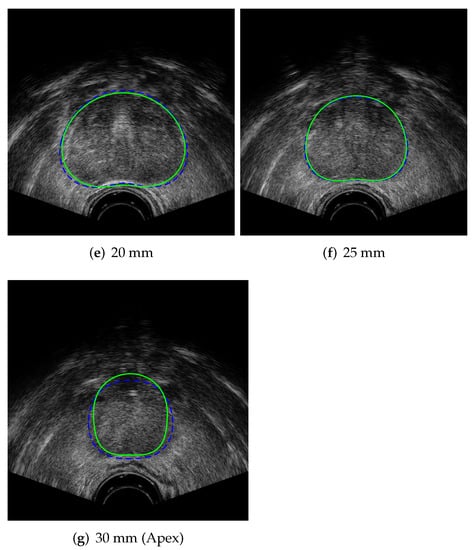

The results of running the superpixel algorithm on an input TRUS image, showing the pixel cluster, superpixel regions, and adjacency graph during multiple algorithm iterations, are given in Figure 6. The boundaries of the pixel clusters are indicated with blue lines and the centroids of the pixel clusters are shown as blue dots in Figure 6a,d,g. The superpixel region boundaries are designated with green lines and the region centroids are shown in Figure 6b,e,h. Red dots are used to indicate the centroids of each of the regions (which are also the graph vertices) in Figure 6b,c,e,f,h,i. The region adjacency graph is drawn in Figure 6c,f,i, where a red line between two region centroids represents a graph edge.

Figure 9.

Output of superpixel algorithm in TRUS image frame with region borders shown in green and region centroids indicated with red dots.